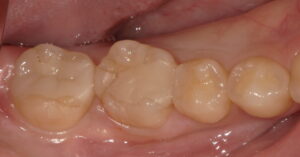

術前:右下6番(写真左から2番目)にセラミックの破折が認められます。